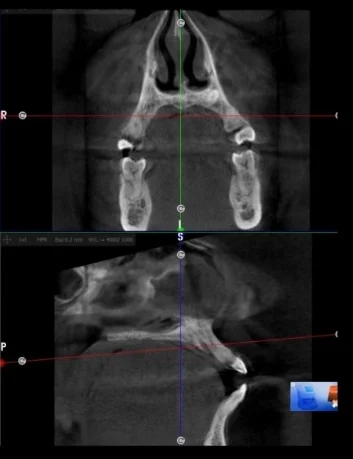

CBCT Dental

(Tomografía Cone Beam)

La CBCT o Tomografía Cone Beam es una tecnología avanzada que permite obtener imágenes 3D de los dientes, huesos, encías y estructuras faciales. A diferencia de las radiografías tradicionales, la CBCT ofrece una visión más detallada y precisa, lo que ayuda a los dentistas a realizar diagnósticos exactos y planificar tratamientos como implantes dentales, ortodoncia y cirugía oral con mayor seguridad y eficiencia. Este procedimiento emite una dosis de radiación mucho menor que los TAC convencionales, lo que lo convierte en una opción más segura para el paciente.